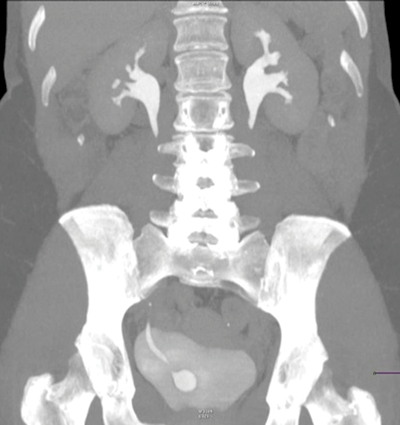

Right sided ureterocoele, with a normal upper tract.

Simple (intravesical) 25% or ectopic 75%.

Majority of ectopic ureterocoeles are associated with a duplex collecting system.